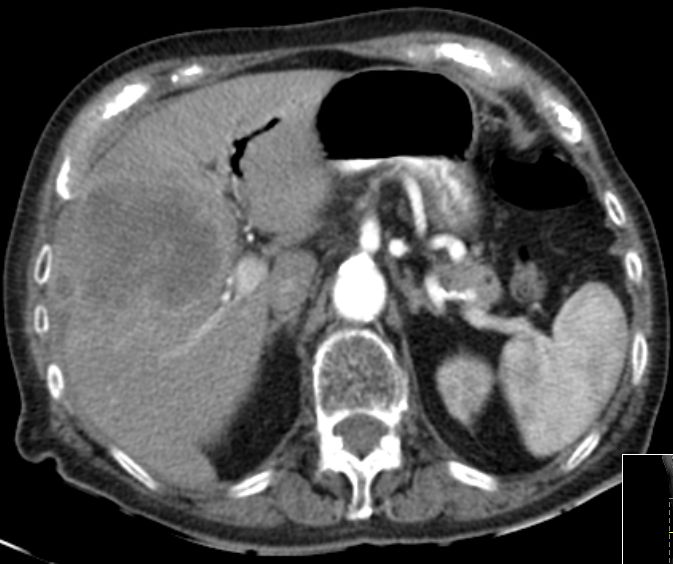

86-jähriger Mann, bei dem vor 9 Monaten eine Cholezystektomie wegen gedeckt perforierter Cholezystitis vorgenommen wurde. Jetzt Verdacht auf Leberabszess. Die laparoskopische Biopsie ergab ein Adenokarzinom. Die Nachbefundung der Gallenblase erbrachte immunhistochemisch den Nachweis eines Gallenblasenkarzinoms. | ||